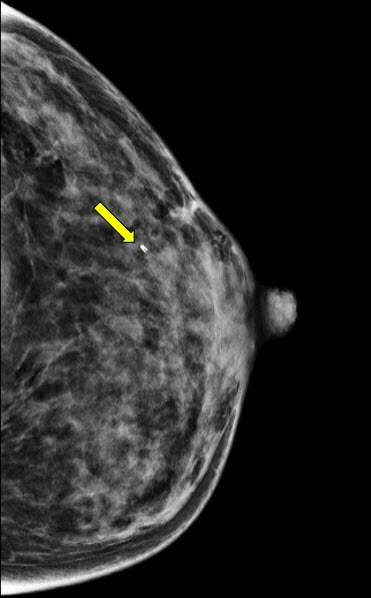

Figure 4. Post-biopsy craniocaudal mammogram confirms post-biopsy micro-clip placement.

- Perform a post-procedure mammogram to demonstrate accurate placement of the micro-clip (fig 4)